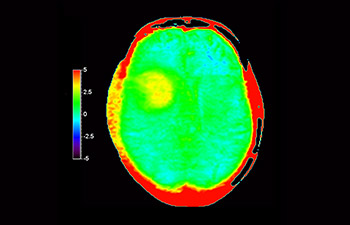

z użyciem metody 3D APT